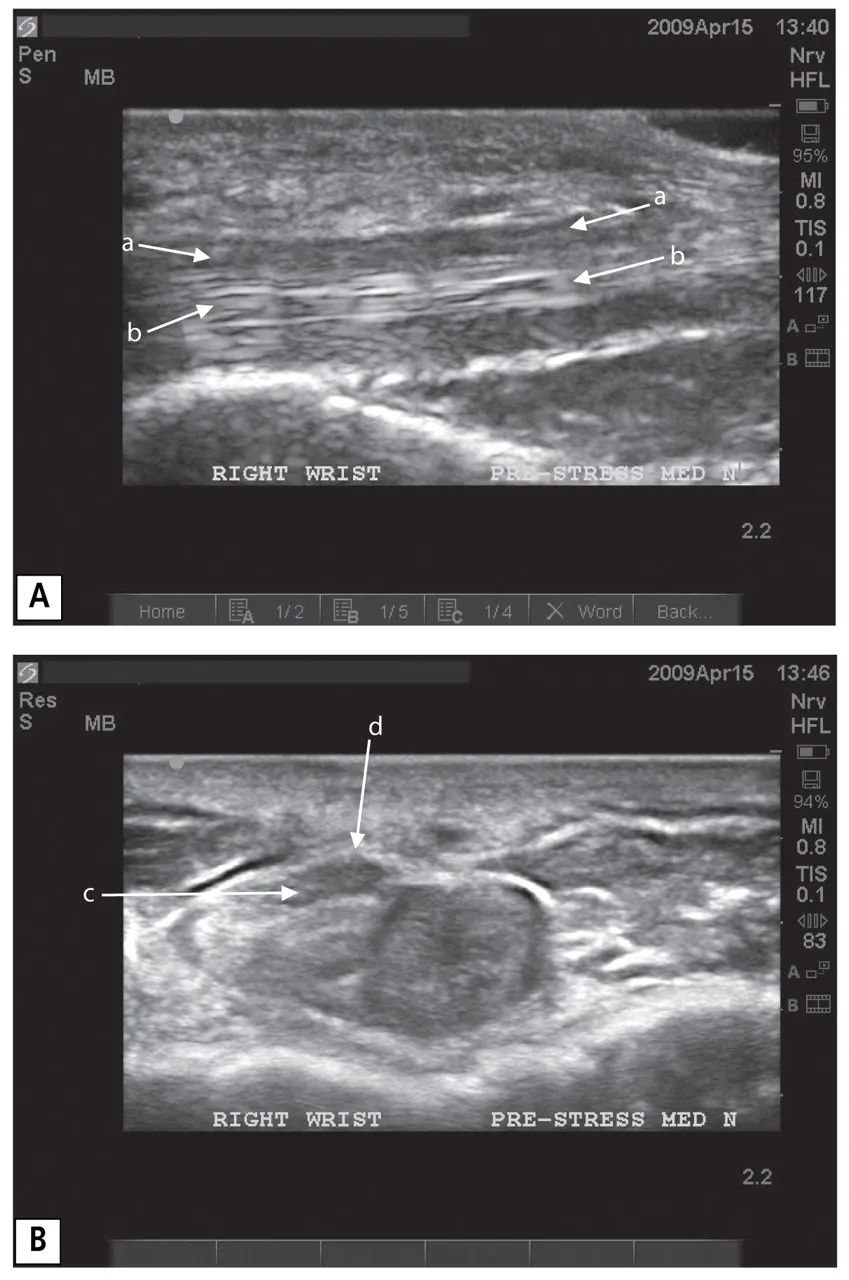

圖三

一名24歲男性腕管綜合征患者的右手腕的預應力超聲圖像(病例1)。在縱向視圖(A)中,正中神經(jīng)是較暗的、低回聲的線性結構,從圖像的左側穿過,幾乎到達右側(箭頭a)。在神經(jīng)下方有一個較亮的、高回聲的線性結構,其上有一個纖維狀的物體,這是屈肌腱(箭頭b)。在橫向圖像(B)中,正中神經(jīng)是位于左上方中央的橢圓形深色結構(箭頭c),就在較亮的腕橫韌帶(箭頭d)下方。